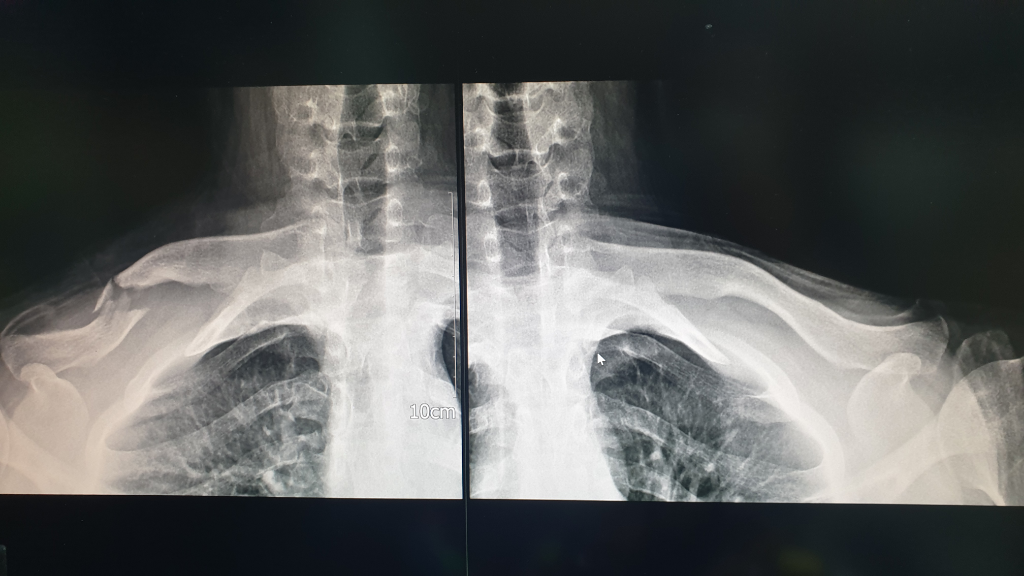

쇄골이 부러졌습니다 비수술로 진행하려는데 도움되는것이 있을까요?

단축은 최대 1cm이라 하고 선생님은 수술을 권했지만

제가 가능성이 있다면 비수술로 치료하고 싶다하여

비수술로 진행하게 되었습니다.

• 1번 째 사진

• 2번 째 사진